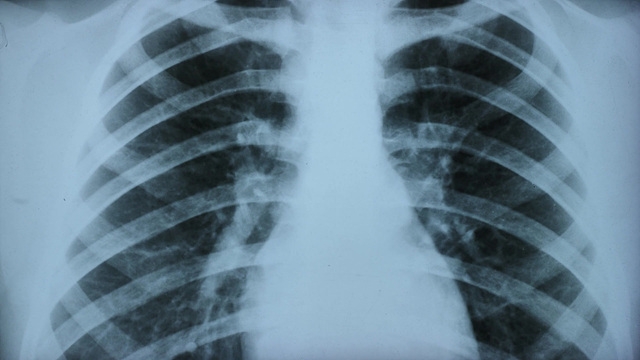

(출처-모션엘리먼츠)

미국 도널드 트럼프 행정부가 추진하는 환경규제 완화 등의 정책이 미국인들의 폐질환을 증가시켜 조기사망을 확대시킬 수 있다는 연구결과가 나왔다.

미국 하버드의대, 케임브리지 건강협회, 메세추세스종합병원, 뉴욕시립대, UC샌프란시스코 등의 폐질환 전문의와 공중보건 전문가들이 참여한 이번 연구는 의료 접근성, 환경 규제, 백신 접종 등 10개 분야의 정책에 대해 분석해보니, 해당 정책들이 폐질환 발생률을 높이고 기존 질환을 악화시키며 치료 접근성을 약화시킬 수 있는 것으로 나왔다.

특히 트럼프 행정부가 1조달러(약 1500조원) 이상 규모의 보건 프로그램 예산을 삭감하며, 공공 건강보험 이용자 수백만명의 의료 접근이 차단될 수 있다는 분석이 나왔다. 예산 삭감이 저소득층의 백신 접종률 저하, 응급 치료 축소, 약물 접근성 감소로 이어질 수 있다는 설명이다. 아담 개프니 하버드의과대학 교수는 "미국인의 폐에 대한 공격"이라며 "향후 몇 년간 수백만명이 불필요하게 사망할 수 있다"고 했다.

대기오염 규제 완화도 주요 요인으로 지목됐다. 연구진은 그을음, 수은, 차량 배출가스 기준 완화가 천식 증가와 호흡기 질환 입원 확대를 초래할 수 있다고 밝혔다. 하버드대학교 기후·보건 및 글로벌환경센터 소장 메리 브라이스는 "오염 기업의 경제적 이익이 미국인의 호흡기 건강보다 우선되고 있다"고 우려했다.

또한 청정에너지 사업 지연과 화석연료 발전소 운영 연장도 대기오염 증가 요인으로 제시됐다. 연구진은 이러한 조치가 장기적으로 폐 건강에 "되돌릴 수 없는 영향"을 미칠 수 있다고 밝혔다.